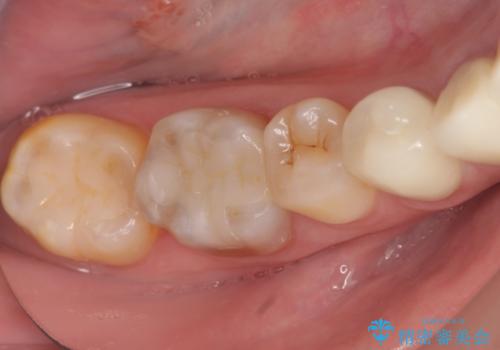

下顎は左側 4 番目から右側 4 番目までの 8 歯と左下 567 ブリッジをオールセラミッククラウンで補綴し、右下67の銀歯はセラミックインレーによる修復を行いました。